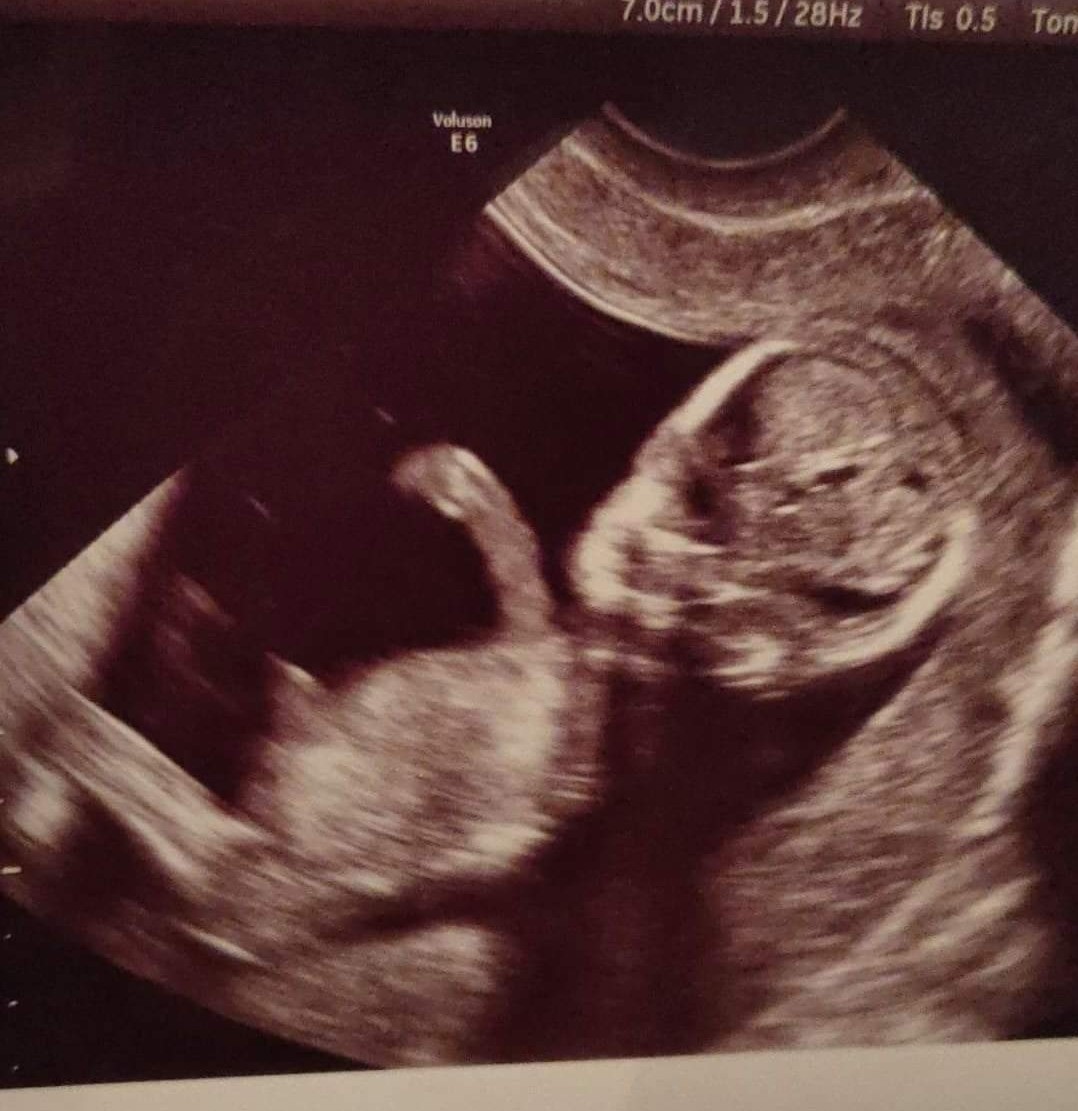

więc chyba nie dam rady. Wczoraj byłam na prenatalnych i wszystko z dzieckiem dobrze

. Ma 5,5 cm, tętno 155 i lekarz stwierdził że chyba dziewczynka

mąż niestety nie mógł wejść ale lekarz nagral całe nasze badanie

nie robiłam dodatkowych badań bo stwierdziłam że skoro na USG wyszło wszystko dobrze to nie będę się denerwować

idę za tydzień do innego lekarza potwierdzić wszystkie dane